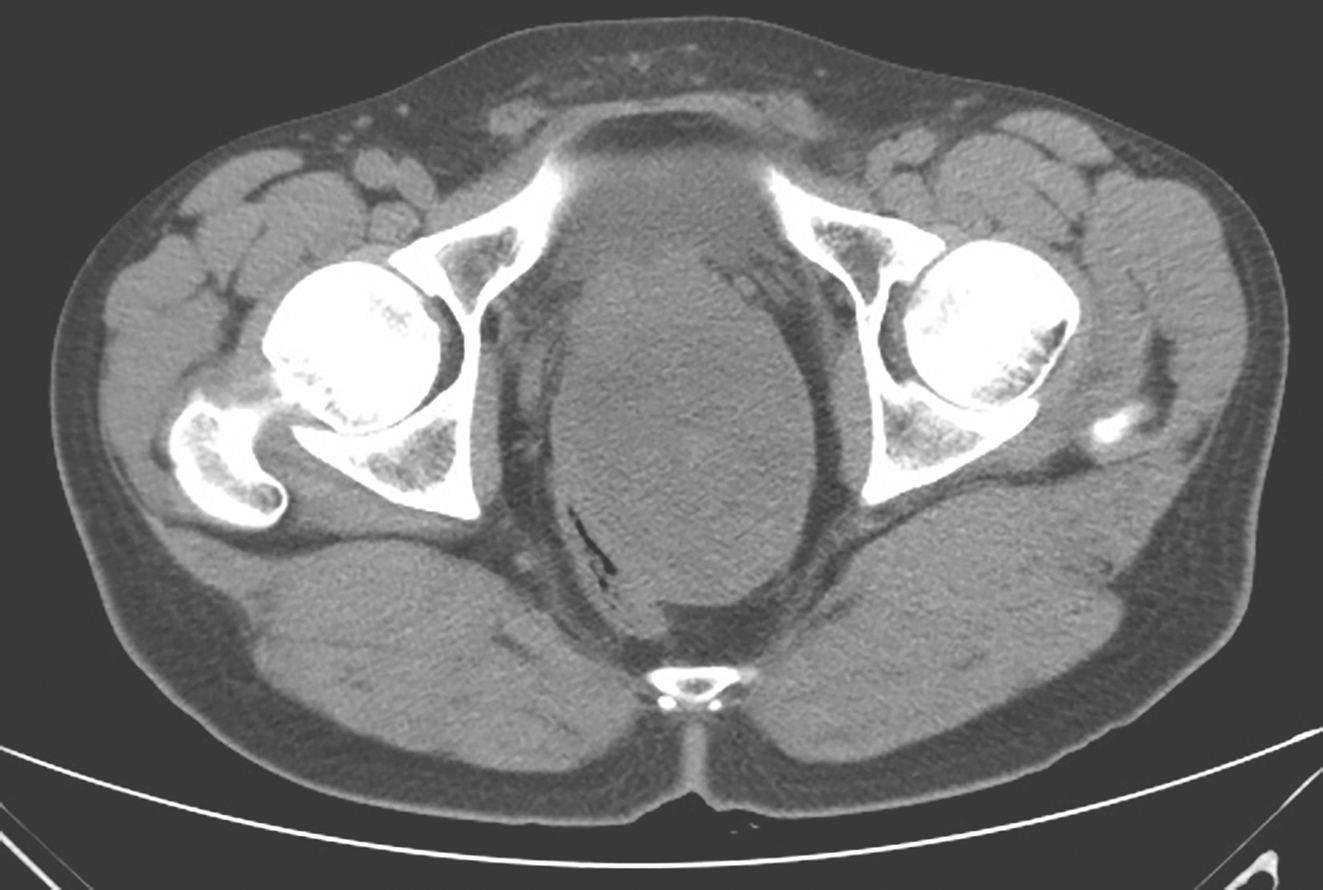

2018年10月胸腹盆腔增强CT(图4):①盆腔见一软组织肿块,大小约9.1cm×7.3cm,边界尚清,挤压相邻直肠、前列腺及双侧精囊,局部分界稍欠清,平扫内部密度不均,可见点状及片状稍高密度灶,增强扫描强化不明显;②肝脏大小形态未见异常,表面光滑,肝叶比例协调,肝实质内见小囊状低密度灶,大小约0.3cm,增强扫描未见强化;③腹腔未见液性密度影,腹腔及腹膜后未见明显淋巴结肿大。

图4 术前腹盆腔增强CT表现